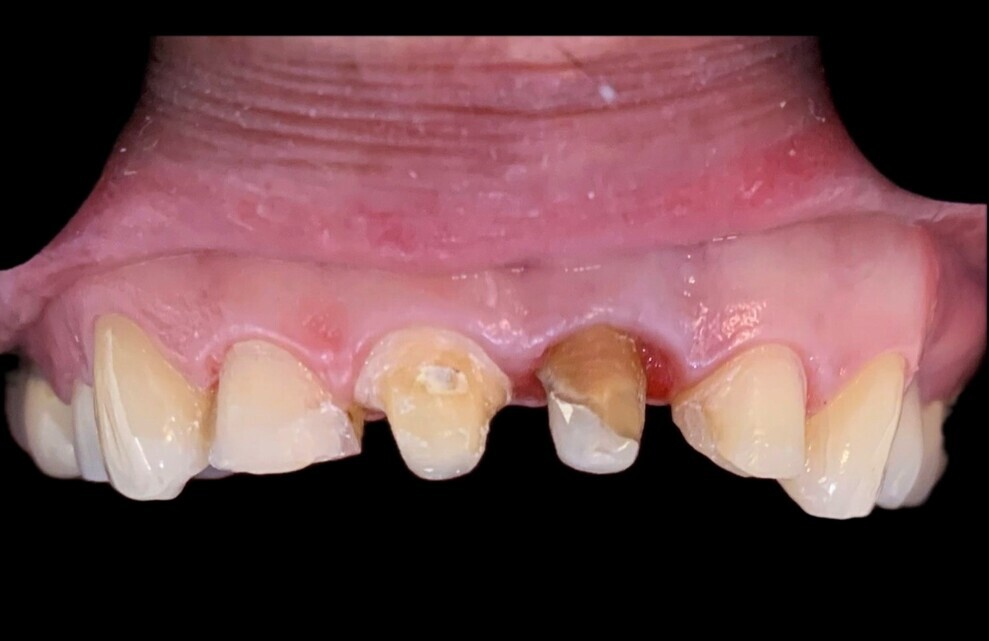

Fig. 4: Clinical situation just before placement of the definitive restoration.

The coronal preparation for the placement of a provisional crown was performed eight weeks after the surgical extrusion procedure. At that appointment, active bone remodelling, mainly at the periapical area, was observed (Fig. 3). This remodelling process is characterised by bone loss at the crestal area in the initial six to eight weeks postoperatively.16 The definitive restoration was placed three months after the initial procedure to provide enough time for the periodontal tissue to heal, thereby preventing post-restorative gingival migration.19, 2 Healthy periodontal tissue, good symmetry of the gingival margin and appropriate ferrule length were observed just before placement of the definitive restoration (Fig. 4).